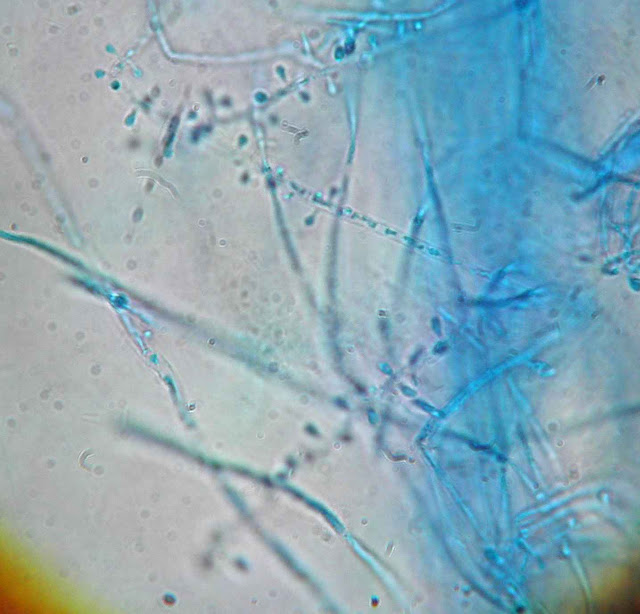

Трихофитон красный (Trichophyton rubrum): изображения и особенности